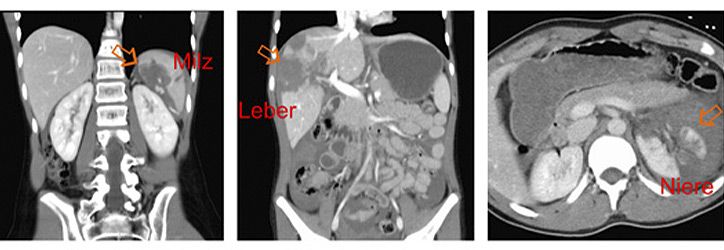

Die Bauchorgane werden in Europa fast ausschließlich durch stumpfe Traumen verletzt. Die Unfallursachen sind altersabhängig und bei Kleinkindern v.a. Stürze, bei Schulkindern zunehmend Sportunfälle und in allen Altersgruppen Verkehrunfälle. Am häufigsten sind Milz, Leber und Nieren (Abbildung) verletzt, seltener die Bauchspeicheldrüse oder der Magen-Darm-Trakt.

Bei Kindern gibt es die Besonderheiten einer noch schwach ausgebildeden Muskulatur des Bauches und flüssigkeitsreichere Organe, die relativ gesehen größer sind als bei Erwachsenen. Führendes Leitsymptom beim Bauchtrauma ist der Bauchschmerz, es können aber auch Übelkeit und Erbechen vorliegen. Wichtig ist zu unterscheiden zwischen isoliertem Bauchtrauma und Patienten mit Mehrfachverletzungen/Polytrauma.

Unsere Kinderklinik hält einen Schockraum vor, in dem verletzte Kinder versorgt werden können und alle diagnostischen Methoden (Röntgen, Sonographie, Computertomographie, Blut- und Urinanalysen) zur Verfügung stehen.

Die meisten Bauchverletzungen im Kindesalter können einer konservativen Therapie auf unserer Kinderintensiv- oder Normalstation zugeführt werden. Sollte eine Operation notwendig sein, so steht rund um die Uhr ein erfahrenes Team aus Kinderchirurgen, Kinderanästhesisten und pädiatrischen Intensivmedizinern bereit.